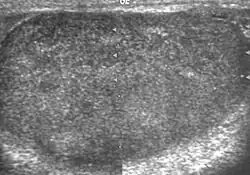

Testicular microlithiasis

Histologically, testicular microlithiasis refers to the scattered laminated calcium deposits in the lumina of the seminiferous tubules. These calcifications arise from degeneration of the cells lining the seminiferous tubules. At ultrasonography, microliths appear as tiny punctate echogenic foci, which typically do not shadow. Although minor microcalcification within a testis is considered normal, the typical US appearance of testicular microlithiasis is of multiple nonshadowing echogenic foci measuring 2–3 mm and randomly scattered throughout the testicular parenchyma [Fig. 25] (Dogra et al., 2003, as cited in Janzen et al., 1992). The clinical significance of testicular microlithiasis is that it is associated with increased risk of testicular malignancy, thus follow up of affected individuals with scrotal sonography is necessary to ensure that a testicular tumor does not develop.

-

Fig. 25. Testicular microlithiasis. Multiple hyperechoic foci without acoustic shadow presenting as a starry sky appearance is seen in the testis.